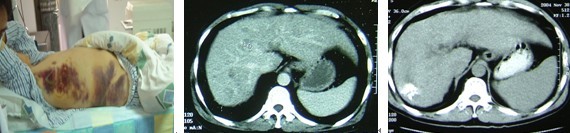

再看一个我自己亲自参加治疗的一位患者,他姓高,住江苏省江阴市。2001年他因眼睛看东西不清楚,在上海被诊断为眼虹膜黑色素瘤,接受了左眼切除手术。2003年,他感到肝区疼痛,在上海XX医院检查,发现肝脏内多个结节,肝活检证实为肝转移。医生告诉他只能生存3个月。他的全家开会讨论,如何安排后事?老高没有灰心,来我院住院,接受了肝转移瘤冷冻消融和联合免疫治疗。患者肝转移瘤停止发展,进而缩小,最后大部消失,恢复正常工作和生活(图8)。虽然最后死于消化道出血,但在“无病”生存的4年半中,他享受了人生,利用这“拾回”的生命,参加江阴抗癌协会,作为志愿者,为癌症病友服务。

老高肝内多个转移,皮下大片出血治疗前,肝内多发性转移灶治疗后肝内癌瘤大部消失

图8 一例转移性黑色素瘤患者的肝CT图像

以上两个患者,病情与美国人报道的患者相似,但我们的病例一个活了14年,一个活了4年多。2010年日本一个国际学术年会上,我对后一个病例作了报道,受到与会者一致称赞。